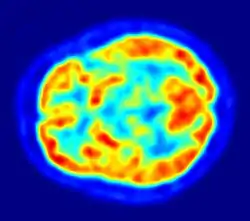

PET imaging with 18F-FDG takes advantage of the fact that the brain is normally a rapid user of glucose. Standard 18F-FDG PET of the brain measures regional glucose use and can be used in neuropathological diagnosis.

Brain pathologies such as Alzheimer's disease greatly decrease brain metabolism of both glucose and oxygen in tandem. Therefore 18F-FDG PET of the brain may also be used to successfully differentiate Alzheimer's disease from other dementing processes, and also to make early diagnoses of Alzheimer's disease. The advantage of 18F-FDG PET for these uses is its much wider availability. Some 18F based radioactive tracers used for Alzheimer's include florbetapir, flutemetamol, PiB and florbetaben, which are all used to detect amyloid-beta plaques (a potential biomarker for Alzheimer's) in the brain.[17]

PET imaging with FDG can also be used for localization of seizure focus. A seizure focus will appear as hypometabolic during an interictal scan.[18] Several radiotracers (i.e. radioligands) have been developed for PET that are ligands for specific neuroreceptor subtypes such as [11C] raclopride, [18F] fallypride and [18F] desmethoxyfallypride for dopamine D2/D3 receptors, [11C] McN 5652 and [11C] DASB for serotonin transporters, [18F] Mefway for serotonin 5HT1A receptors, [18F] Nifene for nicotinic acetylcholine receptors or enzyme substrates (e.g. 6-FDOPA for the AADC enzyme). These agents permit the visualization of neuroreceptor pools in the context of a plurality of neuropsychiatric and neurologic illnesses.